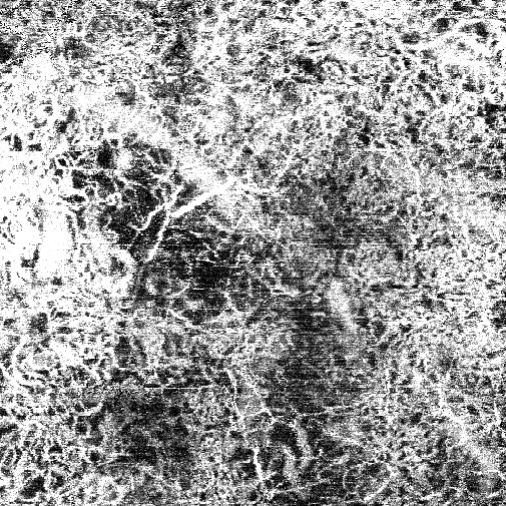

The Data Cleaning phase (Fig. 5) consists of two steps: image cropping and Gaussian filtering for smoothing. In reality, the blood vessel is typically represented as a single piece. However, the process of capturing the OCTA image tends to distort some images, making a vessel appear fragmented, even though it is actually a single continuous thread. Without this phase, relevant information could be lost, or simple artifacts might be misinterpreted as blood vessels.

In Fig. 6, one can observe that the input image has a granular structure, causing the object pixels to appear disconnected. A significant number of background pixels interfere with the visualization of the blood vessels.

We illustrate here how the processing steps lead to the binary image, which contains essential information about the blood vessels. Fig. 9 shows the steps involved in the Data Cleaning phase and Otsu Thresholding.

Fig. 10 presents the image processing techniques and their outcomes at each iteration. The grayscale images progressively approach a binary representation, as seen after the application of multiple binarization techniques. The salt and pepper filter removes part of the noise. In the final image, all components are colored in a way that highlights the principal component. Any remaining noise is removed in Fig. 11, which also shows the result after applying region filling techniques.